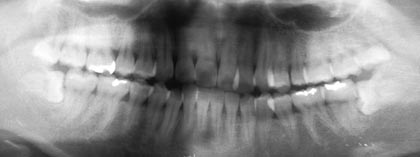

私の下顎の親知らずは難易度的には、どれぐらいのものなのか、また神経麻痺などが残る可能性はどれくらあるのか等まずは相談させていただきたいのですが、予約などは必要でしょうか? はじめましてこんにちわ。 インターネットで検…[→詳細]

右下親知らずが斜めに埋伏しています。他院では、あごの骨を削らないと抜歯出来ないと言われましたが貴院では可能ですか。 右下親知らずが斜めに埋伏しています。 他院(歯科医院2カ所、口腔外科2カ所)では、あごの骨を削らない…[→詳細]

右側の方が奥深いらしく左より大変みたいです。そちらでは、手術の時間が短いとのことですが、やはり顎の骨を削ったりノミで歯を割ったりするのでしょうか? 四日前に親知らずを抜きました。 下顎の左右1本づつ、歯茎の下に完全に…[→詳細]